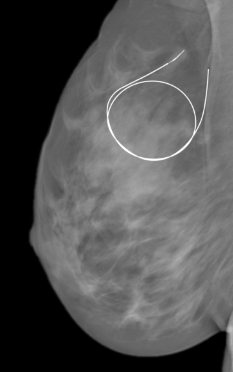

The surgical team watch as the dye collects in the first lymph nodes. This process of